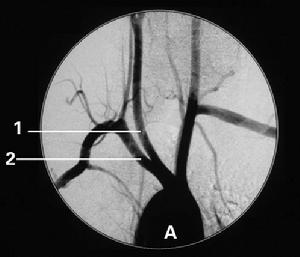

(1)一側鎖骨下或頭臂乾近心段閉塞時,血液流動方向為對側椎動脈→基底動脈→患側椎動脈→患側鎖骨下動脈的遠心段

(2)頭臂乾閉塞時,除按上述方式外同時血液經由後交通動脈→患側頸內動脈→頸總動脈→患側鎖骨下動脈的遠心段。

(3)左鎖骨下動脈和右側頭臂乾同時狹窄,血液經兩側後交通動脈→基底動脈→兩側椎動脈→兩側鎖骨下動脈的遠心段Vollmer等(1973)將所見40例分為:①椎動脈-椎動脈(占66%);②頸動脈-基底動脈(占26%);③頸外動脈-椎動脈(占6%);④頸動脈-鎖骨下動脈(占2%)盜血方式該氏並指出,只有患側頸內動脈發生閉塞性損害時,才會出現頸外動脈-椎動脈分流

腦血管造影①椎動脈和椎動脈;

②甲狀腺動脈和甲狀腺動脈;

③頸升動脈和同側椎動脈及椎前動脈的分支;

④同側頸升動脈和椎動脈的分支;

⑤頸外動脈的枕支和同側椎動脈的肌支(枕椎吻合)從理論上來看基底動脈環是一個良好的側支循環系統,但它受先天發育的限制,尤其是後交通動脈發育不良(占22%),在顱外有大血管阻塞時能嚴重的影響血循環。有人對42例本綜合徵患者的血管造影觀察發現在出現椎-基底動脈供血不足的患者中,其大腦後動脈血流來自頸內動脈(正常由基底動脈而來);大腦後動脈呈胚胎型(即該動脈由頸內動脈向後方直行)以及後交通動脈和大腦後動脈的聯結處有一角度(表示發育不良)者比不出現椎-基供血不足的患者發生率高